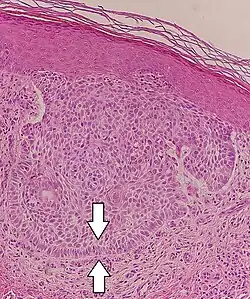

Nodular basal-cell carcinoma

Nodular basal-cell carcinoma (also known as "classic basal-cell carcinoma") accounts for 50% of all BCC.[29] It most commonly occurs on the sun-exposed areas of the head and neck.[30]: 748 [31]: 646 Histopathology shows aggregates of basaloid cells with well-defined borders, showing a peripheral palisading of cells and one or more typical clefts.[29] Such clefts are caused by shrinkage of mucin during tissue fixation and staining.[32] Central necrosis with eosinophilic, granular features may also be present, as well as mucin. The heavy aggregates of mucin determine a cystic structure. Calcification may also be present, especially in long-standing lesions.[29] Mitotic activity is usually not so evident, but a high mitotic rate may be present in more aggressive lesions.[29] Adenoidal BCC can be classified as a variant of NBCC, characterized by basaloid cells with a reticulated configuration extending into the dermis.[29]

Cleft.